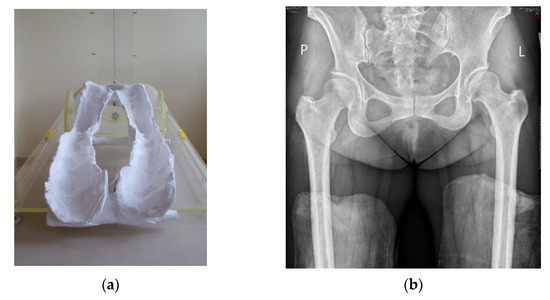

The radiological evaluation included standard digital anteroposterior (AP) radiographs of the hip joints performed preoperatively and on the last follow-up. The patient’s position during the examination was standardized: the patient was supine, and the distance between the X-ray machine and the hip joint was 100 cm [14]. Lower limbs were positioned at 20 degrees of internal rotation [15]. To properly position the hip joints in internal rotation, special plaster molds were made with 20° of internal rotation, in which all of the radiographs were taken (Figure 1).

Figure 1. Plaster molds with 20-degree internal rotation of leg (a) in which AP digital radiographs were taken (b).